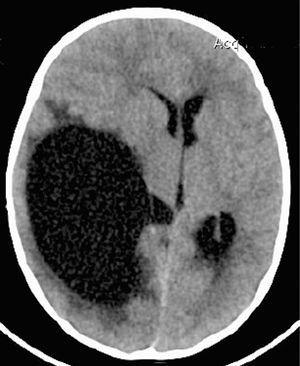

Caso clínico: Niña de 4 meses con clínica de llanto e irritabilidad de varias horas de evolución. Padres refieren 2 episodios de hipotonía sin movimientos anormales ni desviación ocular aparente. En los antecedentes patológicos resalta una visita a PU de un hospital terciario por un traumatismo banal en brazo derecho. Se trata de una familia inmigrante de bajo nivel sociocultural. A las pocas horas del ingreso presenta convulsión clónica generalizada que cede espontáneamente. A la exploración física se observa estado general regular, petequias puntiformes en abdomen y miembros inferiores. Fontanela anterior normotensa. Pupilas mióticas con escasa respuesta. Letargia e hipotonía, Glasgow: 10. En la TC craneal al ingreso se observa: hemorragia subaracnoidea en tentorio y subdural parafalciana posterior y laminar en convexidad parietal posterior confirmada por angio-RM en la que se descartan malformaciones vasculares. Serie ósea: normal.